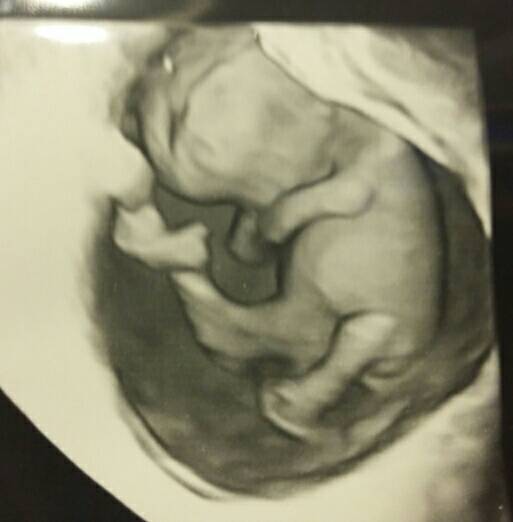

Przeziernosc karkowa zanika lub sie przeksztalca

Bo ja mam wizyte teraz w srode,wg OM bedzie to 11t5dni,a ze dzidzia okolo tydzoen mlodsza to bedzie gdzies tak 10t5d czyli 11 tydzien jak sie liczy...to w srode byloby to usg robione z tym mierzeniem kosci nosowej i przeziernosci czy to jeszcze za wczesnie? Jak myslicie?

Ja bym poczekała. Mi lekarz powiedział , że najlepiej jest zrobić po skończonym 12tc tzn od 12t.1d.